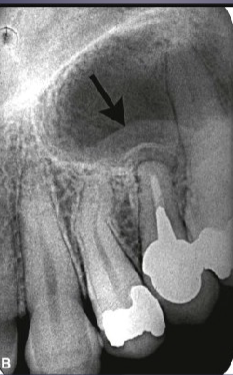

what is the black arrow pointing to

large sequestra caused by acute osteomyelitis